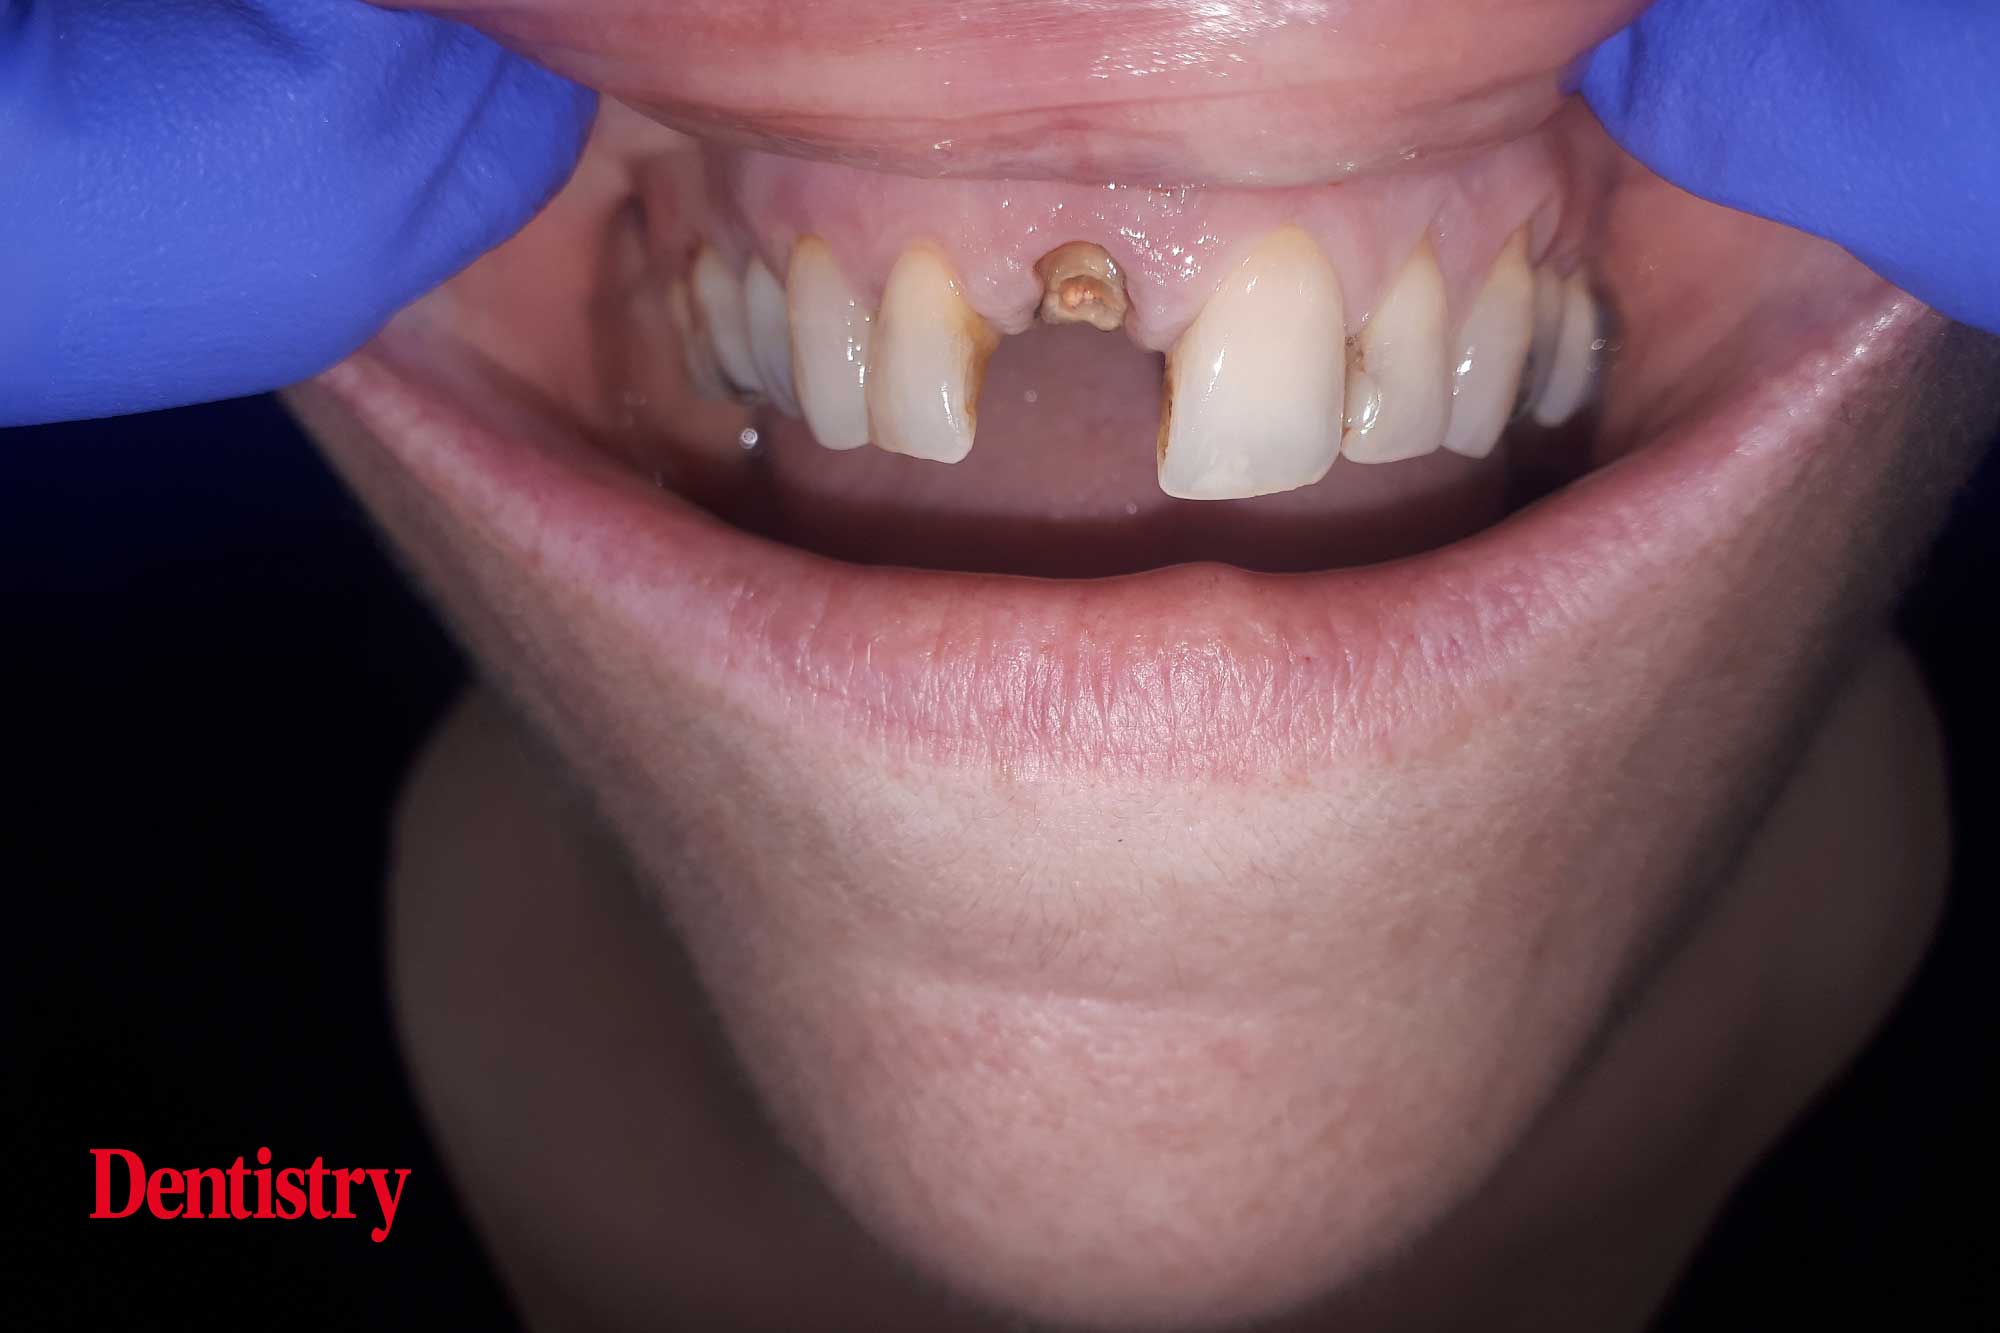

This female patient in her mid-40s was referred to the practice following a traumatic event that resulted in decoronation of the UR1 but was otherwise in good health.

Once the clinical and pre-operative assessments were completed, it was clear that she had good keratinised tissue and a medium smile line.